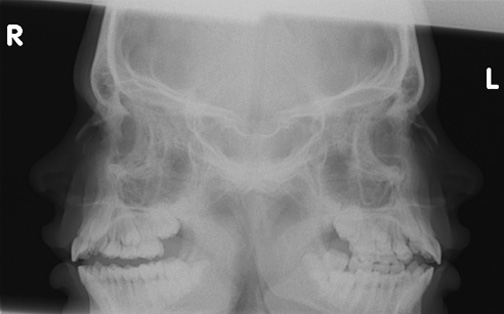

Click the image for labeling.